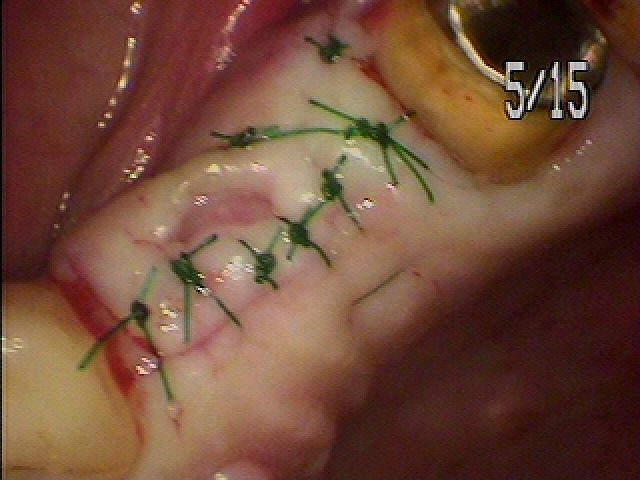

左上インプラント埋入。 2本埋入。| |広島市安佐南区の歯科医院 左上インプラント埋入。 2本埋入。 トップ お知らせ・ブログ 左上インプラント埋入。 2本埋入。 左上インプラント埋入。 2本埋入。 Web診療予約 初めての方へ 選ばれ続ける理由 院内設備について 歯が痛いしみる一般歯科 歯がぐらぐらする歯周病 健康な歯を保ちたい予防歯科 子供の虫歯予防をしたい小児歯科 銀歯をセラミックに審美歯科 白い歯を目指しませんか?ホワイトニング 矯正専門医がいるので安心矯正歯科 抜けた歯を補いたいインプラント・入れ歯 医院案内 スタッフ紹介 メリィハウス歯科クリニックオフィシャルホームページ ラベンダー歯科クリニックオフィシャルホームページ お知らせ・ブログ ホーム 診療科目 一般歯科 歯周病治療 予防治療 小児歯科 審美治療 ホワイトニング 矯正歯科 入れ歯・インプラント マウスピース矯正 初めての方へ 院長・スタッフ 設備紹介 医院案内・アクセス メニューを閉じる